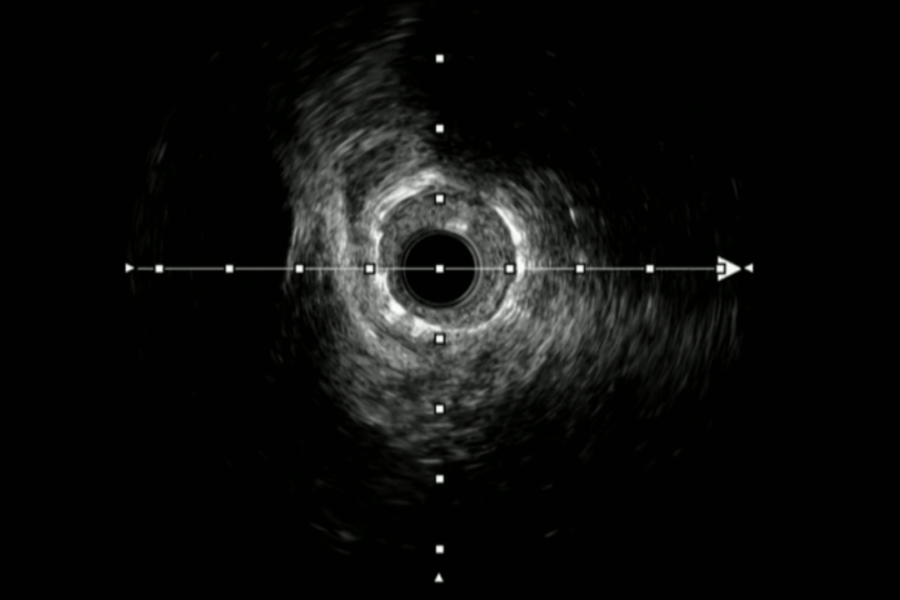

OPCI Live Navigating Complexities: IVUS-Guided ISR CTO with Allen Jeremias and Ziad Ali A monthly live case series that will feature complex and challenging cases with imaging and…ideazioJuly 26, 2024